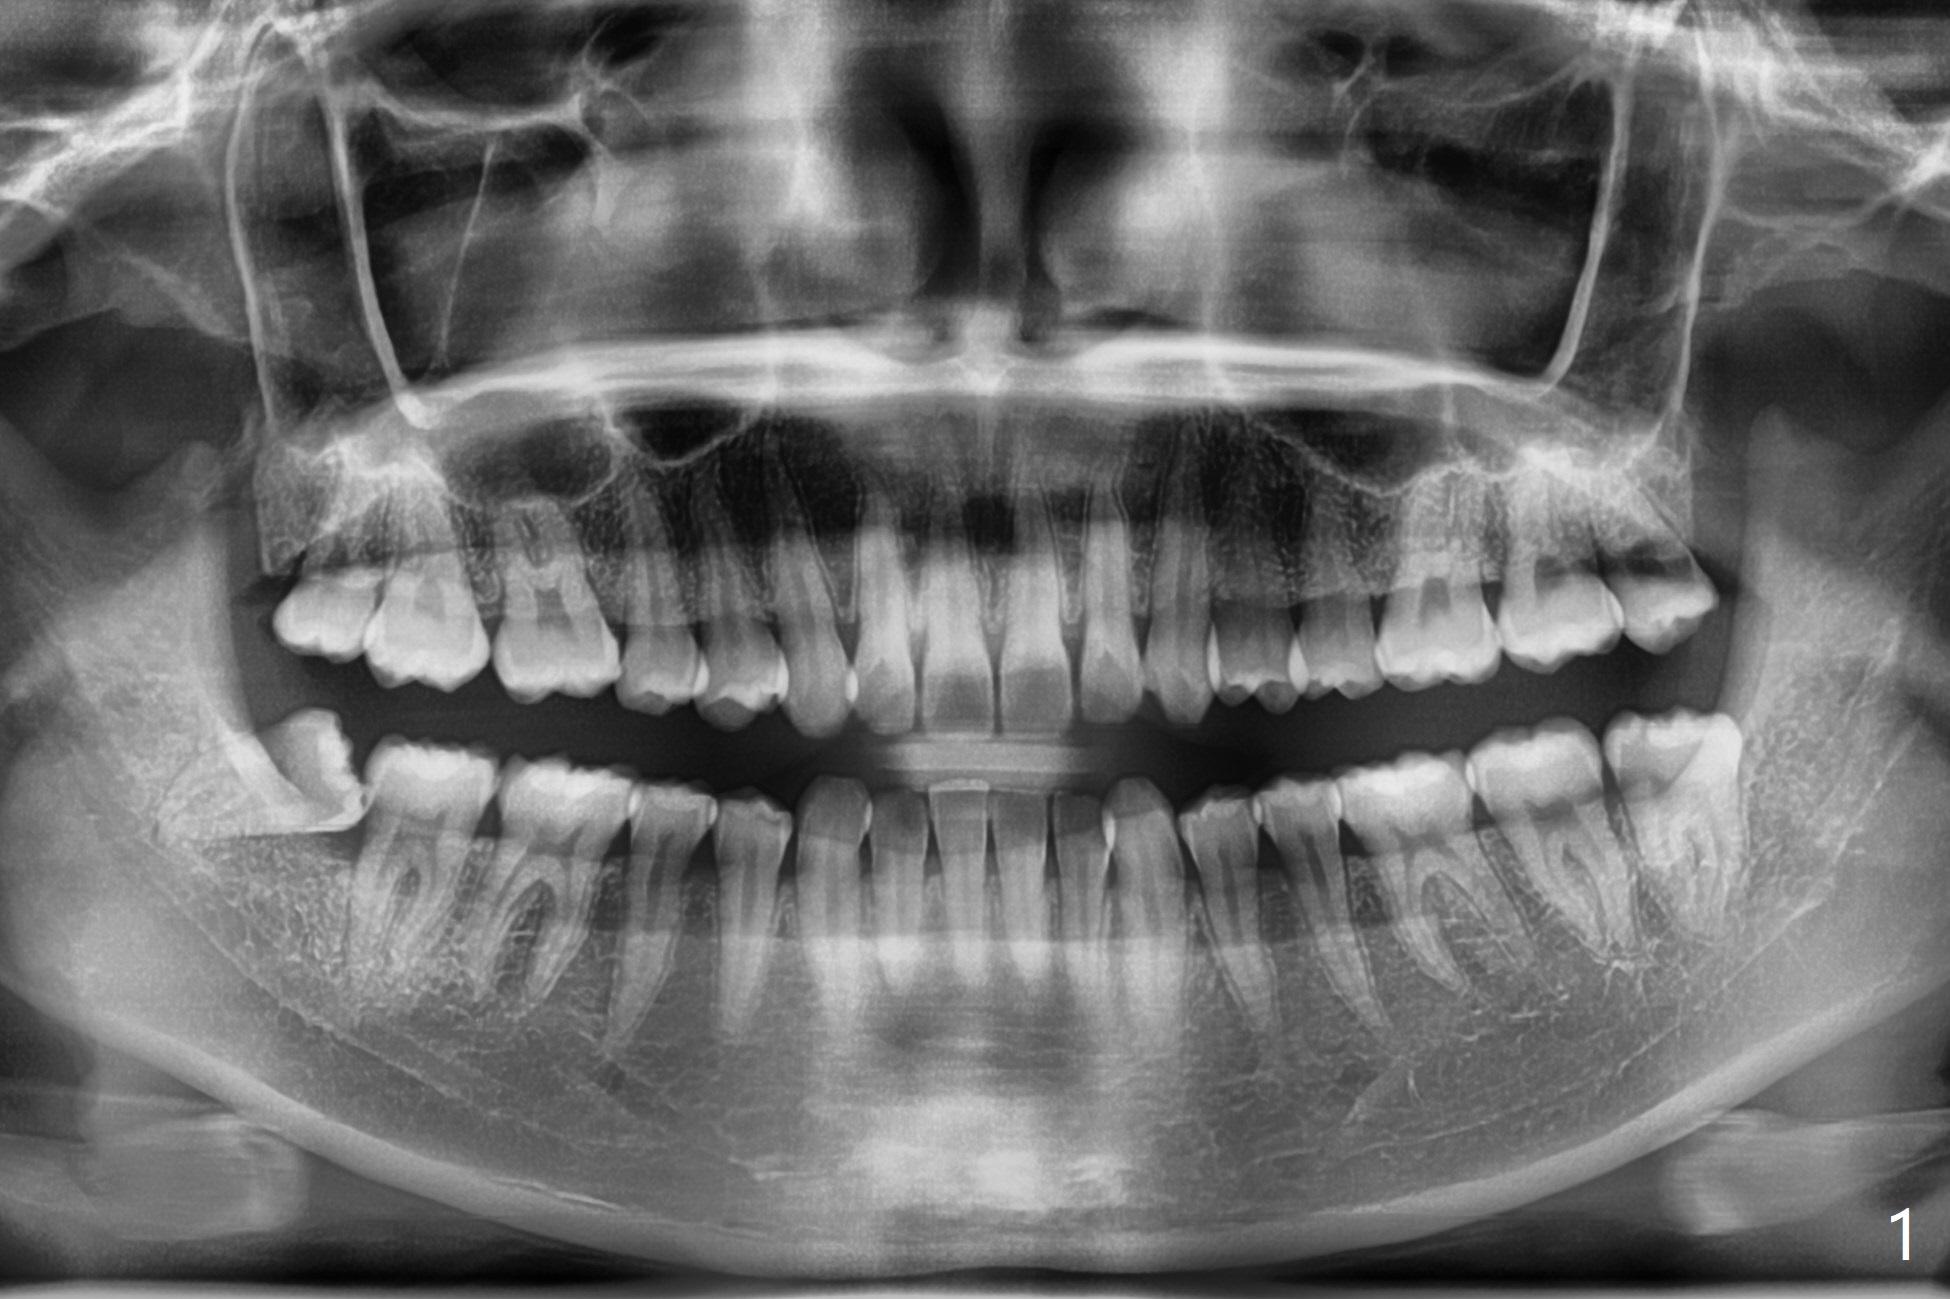

Fused Apices

A 22-year-old woman presents to clinic for #32 extraction at the recommendation of her grandmother (ex-dentist, Fig.1). It is difficult to anesthetize the tooth, which needs to be sectioned multiple times, including to split the roots. To prevent dry socket Osteogen plug is placed, followed by 4-0 plain gut suture.